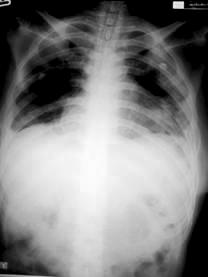

ภาพที่ 1. ภาพฉายรังสีทรวงอก เมื่อวันที่ 7 ธันวาคม พ.ศ. 2548

ที่โรงพยาบาลชุมชน พบว่ามีเยื่อหุ้มปอดหนากว่าปกติ

และมีน้ำในช่องเยื่อหุ้มปอด.

ผู้ป่วยเริ่มมีอาการไอมีเสมหะ หอบ เหนื่อยง่ายเมื่อประมาณ 4 เดือนก่อน นั่งเฉยๆ ก็เหนื่อย หายใจไม่สุด ไม่มีไข้ ไม่เจ็บแน่นหน้าอก ไม่มีอาการแขนขาบวม ระยะแรกผู้ป่วยไปรักษาที่โรงพยาบาลชุมชน อาการไม่ดีขึ้น และมีอาการเหนื่อยมากขึ้นเรื่อยๆ จนต้องนอนรับการรักษาในโรงพยาบาลชุมชน. ผลตรวจทางภาพฉายรังสีทรวงอก พบว่าเยื่อหุ้มปอดมีลักษณะผิดปกติ (มีภาวะหนาตัวขึ้น), มีน้ำคั่งในช่องเยื่อหุ้มปอด และปอดขยายตัวน้อยกว่าปกติ (pulmonary restrictive), ผลการทำ echocardiogram พบว่ามีน้ำคั่งในช่องเยื่อหุ้มหัวใจ (pericardial effusion) และพบว่ามีลิ้นหัวใจรั่วเล็กน้อย แต่การทำงานของ หัวในอยู่ในสภาพปกติ.